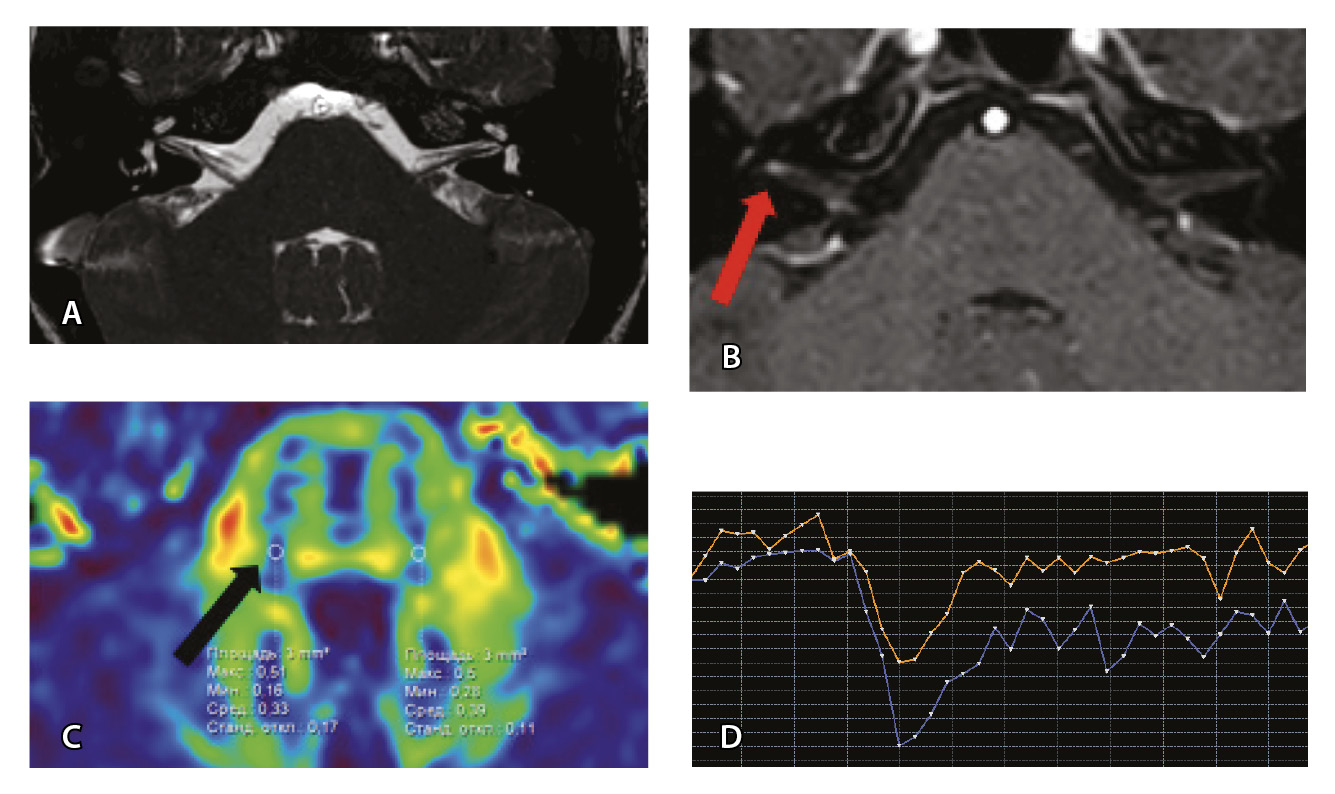

Рис. 3. Пациент Г. Магнитно-резонансная томография (МРТ) головного мозга: А – прицельная T2-SSFP на область мосто-мозжечкового угла; Б – Т1-взвешенное изображение с контрастным усилением; В – диффузионно-тензорная МРТ (фракционная анизотропия); Г – Т2*-перфузия (здесь и далее графики перфузии отражают зависимость повышения интенсивности МР-сигнала, то есть накопления контрастного вещества (вертикальная ось) от времени (горизонтальная ось), тем самым иллюстрируя основные показатели перфузии – relCBV, TTP, MTT). На изображениях T2-SSFP патологические изменения на уровне прохождения лицевых нервов во внутренних слуховых проходах (А), повышенное накопление вещества корешками лицевых нервов (Б) не определяются. Показатели фракционной анизотропии (В) и Т2*-перфузии (Г) на уровне моторных ядер лицевых нервов симметричны

Для наглядности представляем МП-МРТ ребенка без выявленных патологических изменений со стороны черепно-мозговых нервов согласно клиническим данным и при МП-МРТ (рис. 3) Исследование с контрастированием у ребенка без НЛН проводилось по другим показаниям для исключения острого демиелинизирующего процесса.